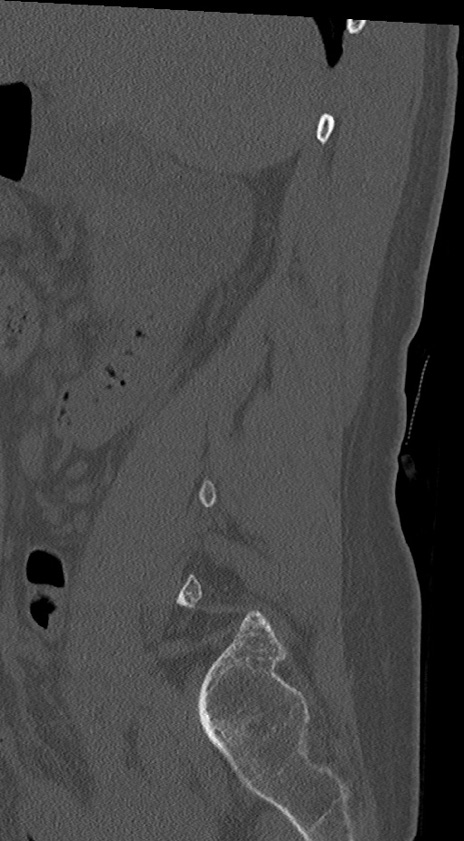

腰椎CT

冠状断像